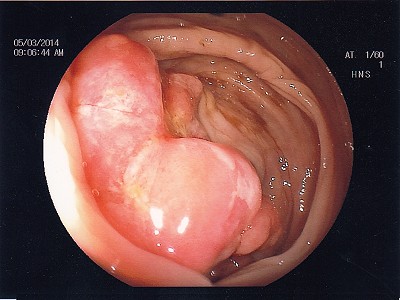

Abb. 2: Das Gebilde des oberen Mastdarmes, auch hier ist die Ent- fernung des Tumors mittels Darmspiegelung nicht mehr möglich. Abb. 2: Das Gebilde des oberen Mastdarmes, auch hier ist die Ent- fernung des Tumors mittels Darmspiegelung nicht mehr möglich.